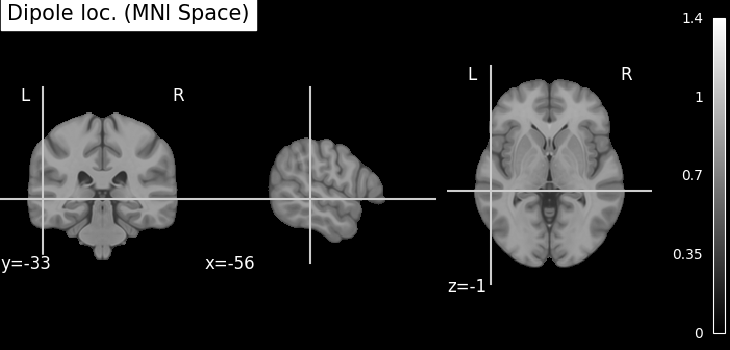

Plot the result in 3D brain with the MRI image using Nilearn In MRI coordinates and in MNI coordinates (template brain)

subject = "sample"

mni_pos = dip.to_mni(subject=subject, trans=fname_trans, subjects_dir=subjects_dir)

mri_pos = dip.to_mri(subject=subject, trans=fname_trans, subjects_dir=subjects_dir)

# Find an anatomical label for the best fitted dipole

best_dip_idx = dip.gof.argmax()

label = dip.to_volume_labels(

fname_trans, subject=subject, subjects_dir=subjects_dir, aseg="aparc.a2009s+aseg"

)[best_dip_idx]

# Draw dipole position on MRI scan and add anatomical label from parcellation

t1_fname = subjects_dir / subject / "mri" / "T1.mgz"

fig_T1 = plot_anat(t1_fname, cut_coords=mri_pos[0], title=f"Dipole location: {label}")

try:

template = load_mni152_template(resolution=1)

except TypeError: # in nilearn < 0.8.1 this did not exist

template = load_mni152_template()

fig_template = plot_anat(

template, cut_coords=mni_pos[0], title="Dipole loc. (MNI Space)"

)